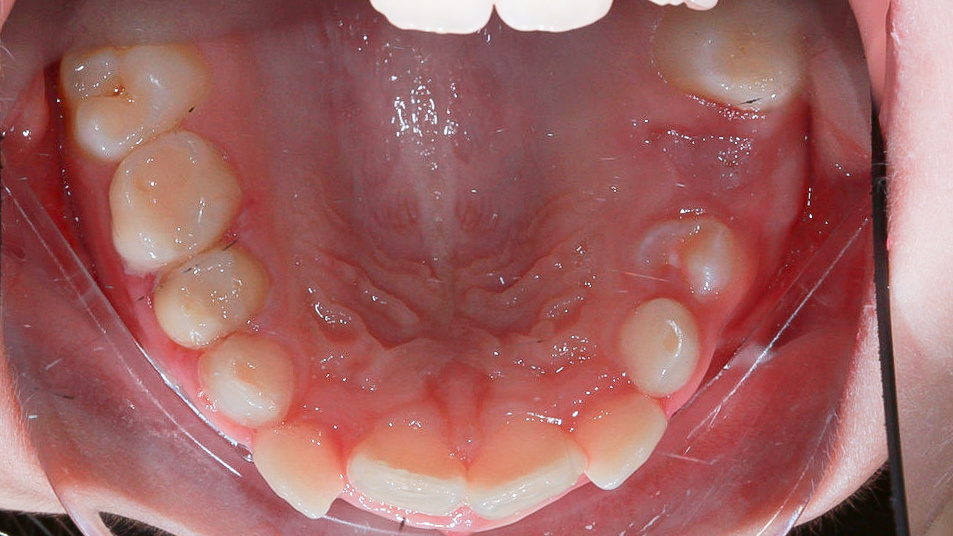

Алина попала на прием к ортодонту в 9 лет. Это не было ее первым визитом. Мама приводила девочку на консультацию и раньше, но тогда необходимости в коррекции еще не было.

Причины, по которым Алину записали к ортодонту:

❗️узкая нижняя челюсть

❗️криво прорезались верхние «двойки»

❗️«единицы» под наклоном

К моменту начала лечения у Алины прорезалось по 6 постоянных зубов на нижней и верхней челюсти. На верхней челюсти это резцы: 1.1, 2.1, 1.2 и 2.2, а также моляры 1.6 и 2.6. Ни нижней челюсти резцы 3.1, 4.1, 3.2 и 4.2, а также моляры 3.6 и 4.6.